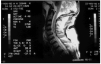

En la evolución posterior presentó hipotonía en miembros inferiores con arreflexia osteotendinosa y reflejo bulbocavernoso negativo. En los miembros superiores conservó la movilidad de ambos bíceps y extensores del carpo izquierdo con un nivel sensitivo C4. Se realizó resonancia magnética nuclear (RMN) medular, demostrándose imagen hiperintensa a nivel C5-D2 (fig. 1) sugestiva de isquemia medular.

Figura 1. Imagen hiperintensa a nivel C5-D2 sugestiva de isquemia medular.